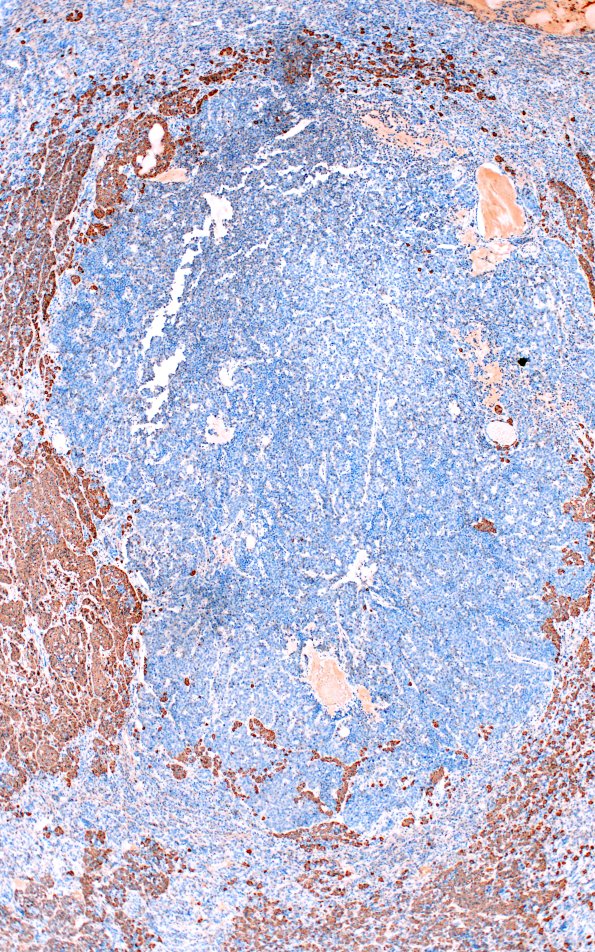

Washington University Experience | NEOPLASM (SELLAR) | Pituitary Adenoma - Pituitary Neuroendocrine Neoplasm | Multiple Microadenomas | 1E2 Multiple microadenomas (Case 1) 4X ACTH Area A

Microadenoma A shows no ACTH immunoreactivity. (ACTH IHC)